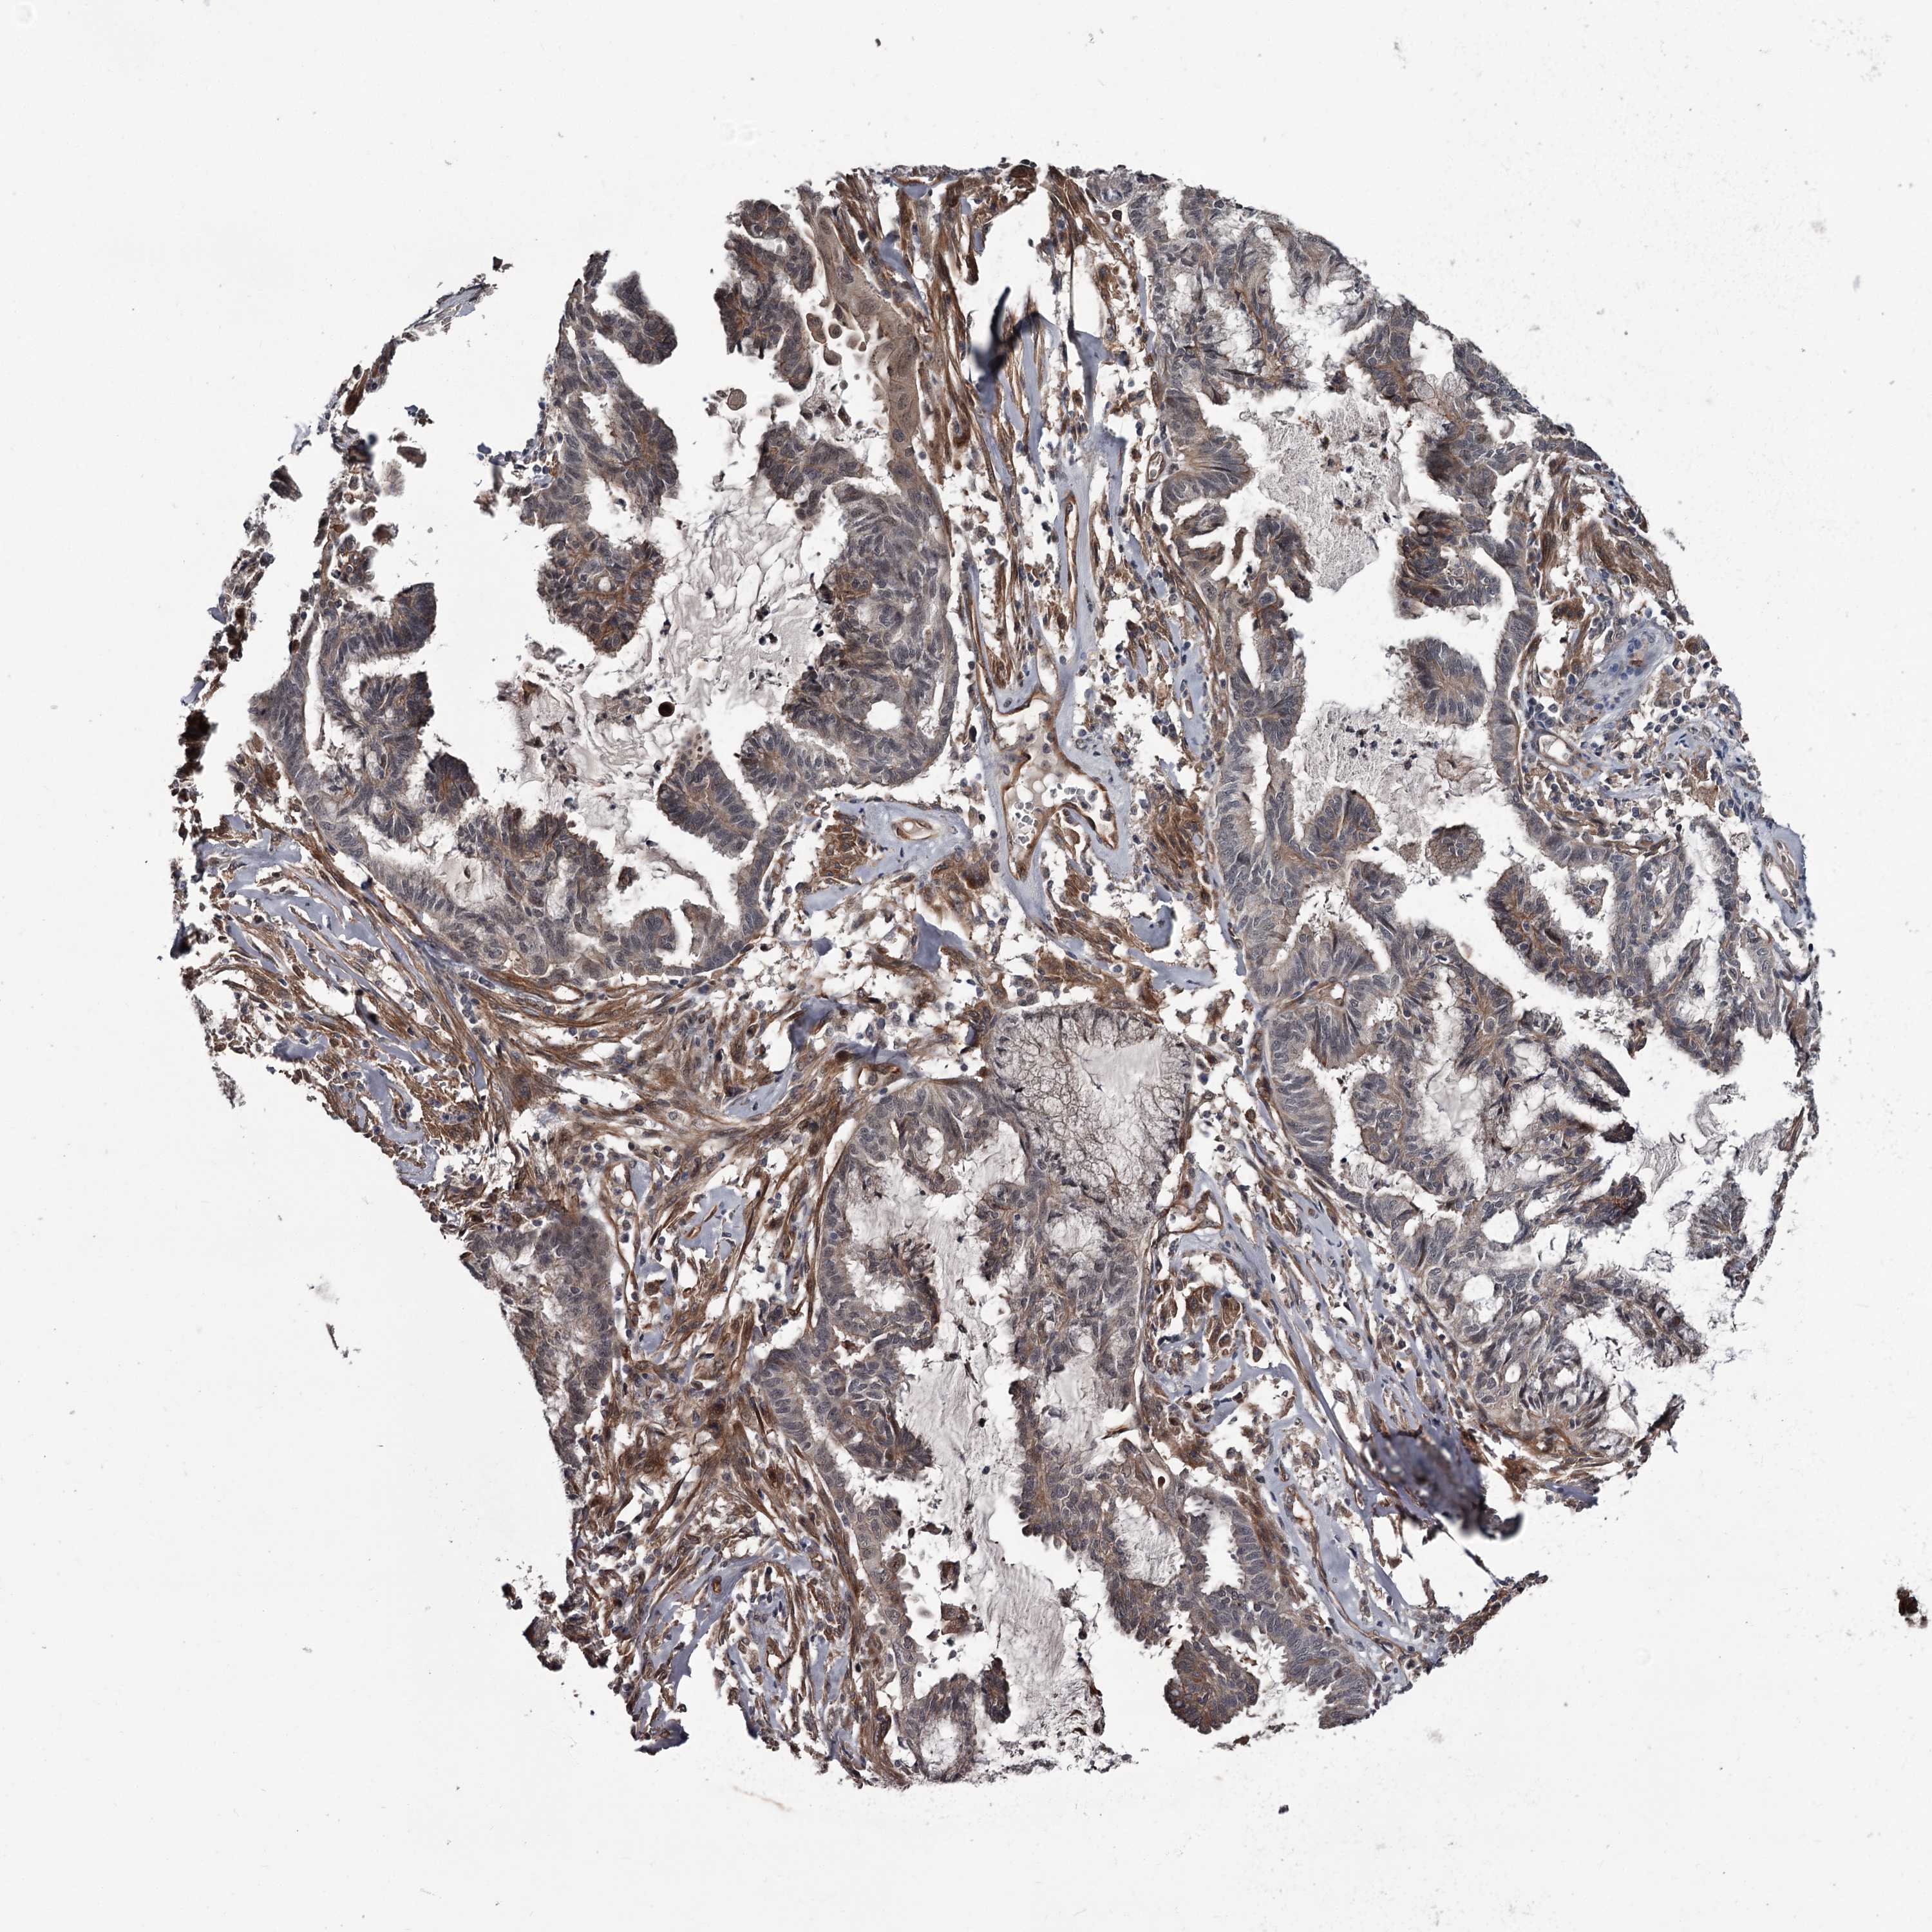

ENDOMETRIAL CANCER - Protein expressioni

A mouse-over function shows sample information and annotation data. Click on an image to view it in a full screen mode. Samples can be filtered based on level of antibody staining by selecting one or several of the following categories: high, medium, low and not detected. The assay and annotation is described here.

Note that samples used for immunohistochemistry by the Human Protein Atlas do not correspond to samples in the TCGA dataset.

Antibody stainingi

Antibody staining in the annotated cell types in the current human tissue is reported as not detected, low, medium, or high, based on conventional immunohistochemistry profiling in selected tissues. This score is based on the combination of the staining intensity and fraction of stained cells.

Each image is clickable and will lead to virtual microscopy that enables deeper exploration of all samples and also displays staining intensity scores, fraction scores and subcellular localization as well as patient and tissue information for each sample.

Antibody HPA038562

Staining

High

Medium

Low

Not detected

Intensity

Strong

Moderate

Weak

Negative

Quantity

>75%

75%-25%

<25%

None

Location

Nuclear

Cytoplasmic/membranous

Cytoplasmic/membranous,nuclear

Adenocarcinoma, NOS

Adenocarcinoma, metastatic, NOS